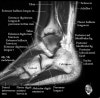

- Axial section

Axial PD fat suppression evaluates the tendons and ligaments of the ankle particularly after acute/subacute injuries. It also is sensitive to talar dome osteochondral defects. Alternatively, a T2 sequence can be used to eliminate magic angle artifact that may occur as the tendons travel around the malleolar turns.

Tibiofibular ligaments

Lateral ankle ligaments

Deltoid and spling ligaments

Tendon(Achilles, Medial, Lateral, Anterior)